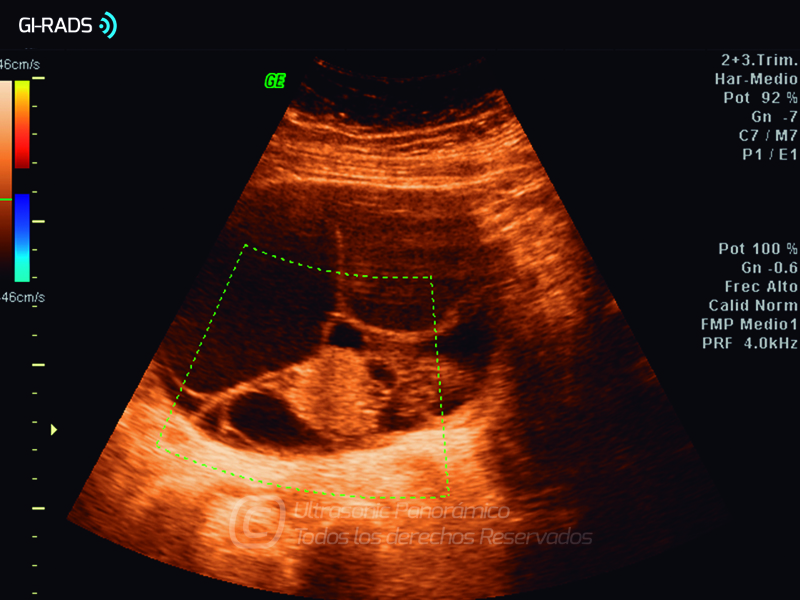

Cáncer Anexial – Áreas Sólidas

• Cáncer Anexial – Áreas Sólidas